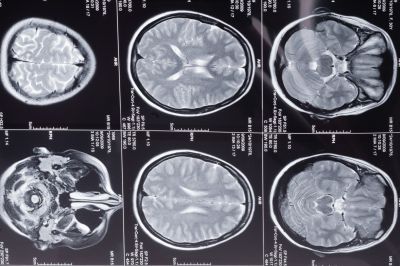

Фото: 123rf.com